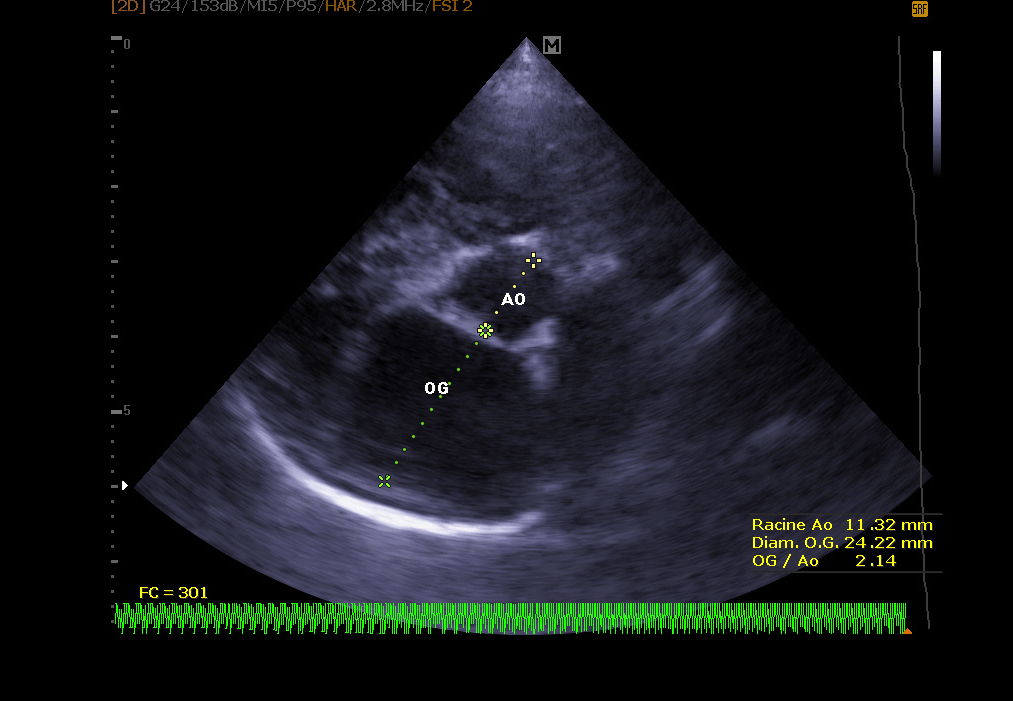

Echokardiographie:

Es ermöglicht die Visualisierung der verschiedenen Teile des Herzens (Wände, Hohlräume, Klappen) und die Identifizierung von Anomalien, die eine korrekte Herzfunktion verhindern. Bei Herzinsuffizienz ermöglicht die Echokardiographie auch eine regelmäßige Überwachung der Herzmorphologie. Es ist dann einfacher, die Behandlung an Ort und Stelle neu einzustellen.